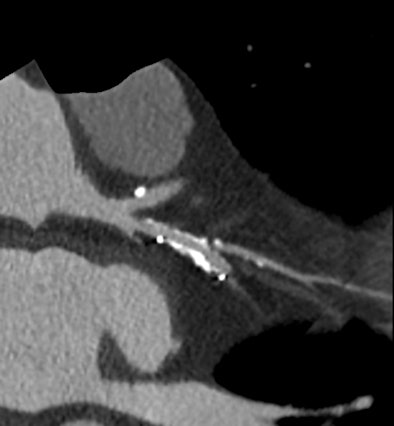

High-definition cardiac CT image obtained on GE Healthcare's Discovery CT750 HD shows stenosis adjacent to stent. (Provided by GE)